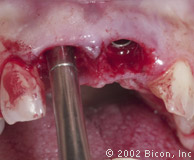

Подготовка для установки временной конструкции

Установка временной конструкции

Рентгенограмма сразу после первого посещения

Две части: имплантант и абатмент. Никаких винтов и дополнительных креплений, которые создают условия для проникновения бактерий из-за неплотного прилегания частей конструкции.